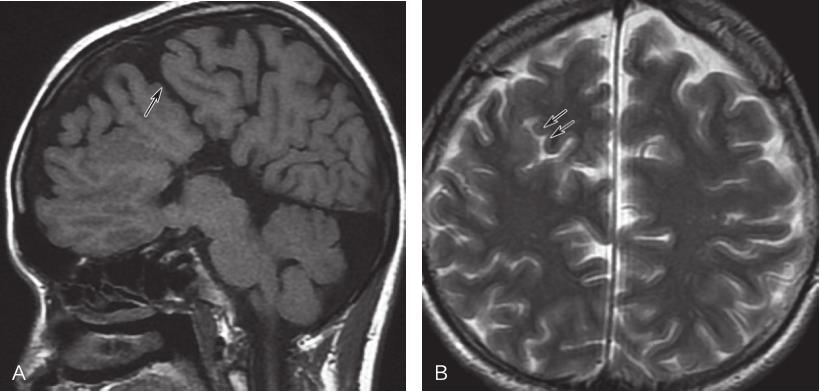

图2-3-3 胼胝体完全缺失伴脑裂畸形MRI表现

A.矢状位T 1 WI胼胝体完全性缺失并脑裂畸形(箭);B.横断位T 2 WI示右侧额叶脑裂畸形(箭)

图2-3-7 胼胝体变薄MRI表现

矢状位T 1 WI示胼胝体结构完整,形态明显变薄